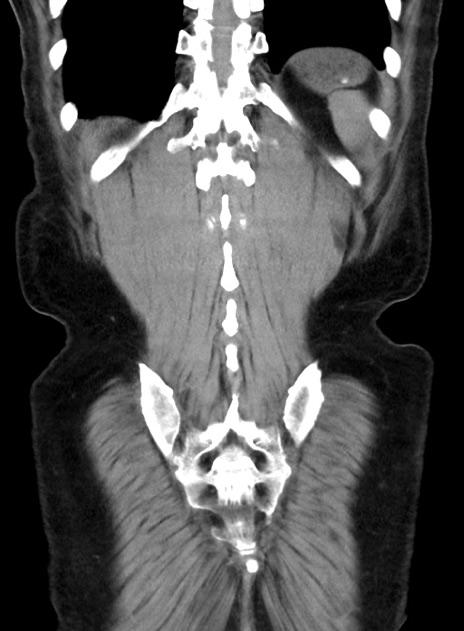

症例38(冠状断像)

横断像